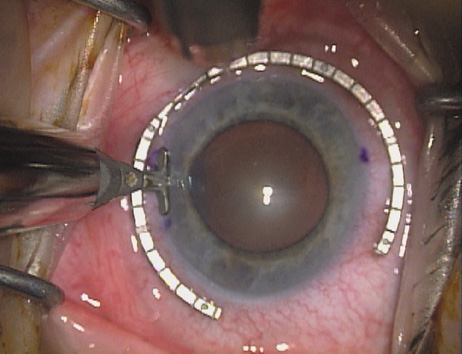

Case 2 is a 79-year-old woman who presented with a very dense left cataract. Her refraction was recorded at −2.25 +2.75 × 125 with a difficult end point. Her manual keratometry and topography measurements were consistent and revealed slightly less than 1.75 D at 120 degrees. Because of the questionable refraction, greater value was placed on the corneal measurements. Based upon the cataract nomogram, the plan was for paired LRIs of 40 degrees to be placed over the steep 120-degree axis (Figs. 1219).

Fig. 13. The incision is begun 20-degrees to one side of the centering mark. (Reprinted from Hardten DR, Lindstrom RL, Davis EA. Phakic Intraocular Lenses: Principles and Practice. Thorofare, NJ: SLACK Incorporated, 2004, with permission.)